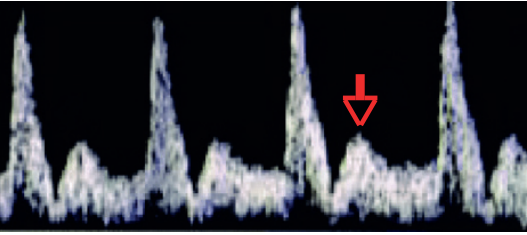

2. Dopplervelocimetria Fetal

Este método avalia o fluxo sanguíneo em diferentes territórios vasculares, refletindo a adaptação fetal à insuficiência placentária.

- Artérias Uterinas: Aumento da resistência neste vaso materno pode predizer o risco de pré-eclâmpsia e RCF.

- Artéria Umbilical (AU): É o primeiro vaso a se alterar. Um aumento no seu Índice de Pulsatilidade (IP) reflete o aumento da resistência na placenta. A progressão da doença leva ao fluxo diastólico zero (Diástole Zero) e, finalmente, ao fluxo reverso (Diástole Reversa), que são marcadores de grave comprometimento placentário.

- Artéria Cerebral Média (ACM): Em resposta à hipoxemia, o feto redistribui o fluxo sanguíneo para órgãos nobres, como o cérebro. Isso causa uma vasodilatação na ACM, detectada como uma queda em seu IP. Este fenômeno é conhecido como

centralização fetal ou “brain-sparing”. A centralização é um mecanismo de adaptação e, isoladamente, não define sofrimento fetal. - Ducto Venoso (DV): É um dos últimos vasos a se alterar. O aumento do seu IP ou a presença de uma onda “a” ausente ou reversa indicam falência do coração direito devido à sobrecarga e se correlacionam fortemente com acidemia fetal.

A sequência de eventos hemodinâmicos é: ↑ IP da AU → ↓ IP da ACM (centralização) → ↑ IP do DV (acidemia = sofrimento fetal).